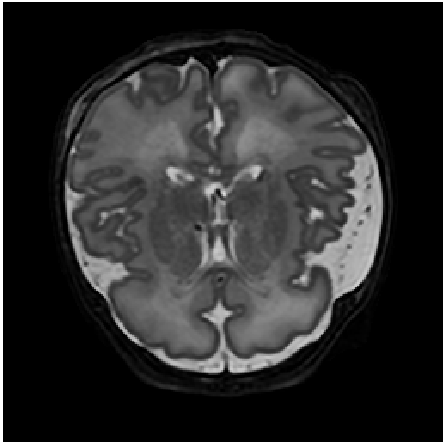

Refer to caption

(a)

(b)

(c)

Figure 4: Qualitative evaluation of reconstruction performance of our method on cardiac cine MRI (ACDC dataset). (a) Original cardiac MRI scan; (b) Its reconstruction and (c) Differences between original (minuend) and corresponding reconstructed (subtrahend) slice. Note that to reconstruct a slice xnsubscript𝑥𝑛x_{n} the mixing coefficient α𝛼\alpha in Equation 1 is set to zero. Blue corresponds to negative and red to positive differences. Image intensities are scaled to a [0,1]01[0,1] range. All difference images use the same color scale [1,1]11[-1,1].

Slice Reconstruction: Results for reconstructed and synthesized slices listed in Table I convey that the proposed approach achieved high reconstruction performance especially in terms of SSIM and PSNR. Figure 4 depicts qualitative results of reconstruction performance for the proposed method on cardiac MRI. The results show that the trained autoencoder can reconstruct high-quality images i.e. input slices. Nevertheless, difference image shown in Figure 4(c) depicts that some high spatial frequency details of the input slice are lacking in the reconstructed slice.